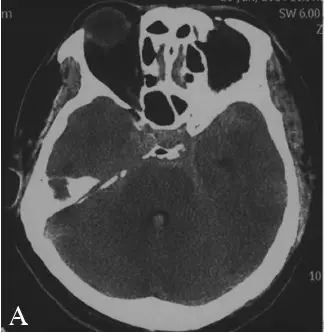

CT:头颅CT提示蛛网膜下腔出血,鞍上池为主,左侧略多,并可见四脑室内积血,无脑积水,Fisher分级4级(图18-3A)。

DSA:急诊行全脑血管造影提示基底动脉下段可见1枚形态不规则囊性动脉瘤(图18-3B)。三维重建后提示基底动脉下段开窗畸形,动脉瘤瘤颈位于开窗近段分叉处,瘤顶有子囊(图18-3C),动脉瘤瘤颈1.85 mm,瘤深5.45 mm,瘤宽2.77 mm。左侧椎动脉造影提示左侧椎动脉仅供血小脑后下动脉(PICA)区域,未汇入基底动脉(图18-3D)。颈内动脉造影未见明显异常。

A:急诊头颅CT提示弥漫性蛛网膜下腔出血及四脑室积血;

B:右侧椎动脉造影示基底动脉下段可见1枚形态不规则囊性动脉瘤;

C:右侧椎动脉造影及3D重建见基底动脉下段开窗畸形并开窗近段分叉处动脉瘤;

D:左侧椎动脉造影提示左侧椎动脉发育不良,仅供血小脑后下动脉(PICA)区域。

图18-3患者术前头颅CT及DSA影像